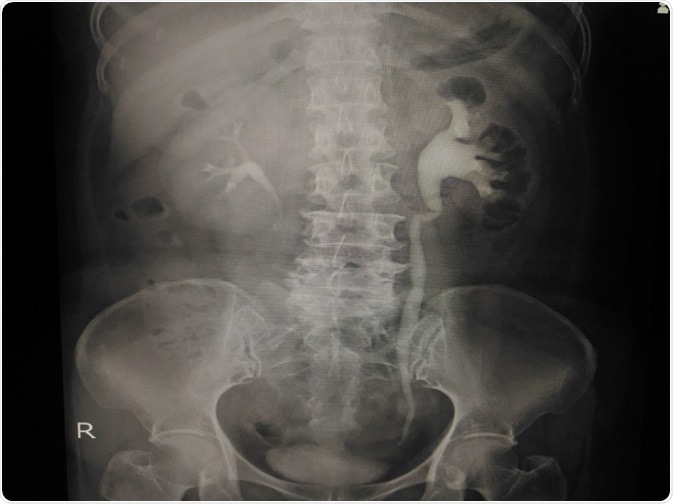

Blur Special Examination I.V.P: Show a 4mm.calcified stone at distal Lt. ureter. Credit: Tonpor Kasa/ Shutterstock.com

Diagnosis involves the use of imaging modalities, such as kidney-ureter-bladder (KUB) radiographs, computed tomography (CT) scans and ultrasound scans. Depending on the indication, pyelography and nuclear scans of the kidney using radioisotopes may also be required.